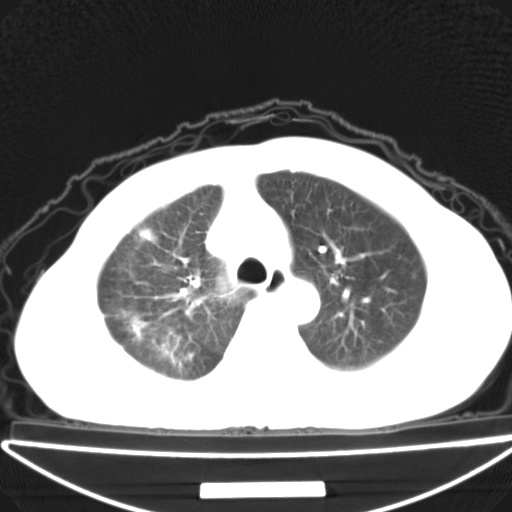

以下是引用jsgdoctor在2008-11-6 22:12:00的发言:[br]右主支气管壁明显增厚,管腔狭窄.考虑为右侧中央型肺癌伴阻塞性炎症\\肺脓肿.

以下是引用zjzjr在2008-11-6 20:25:00的发言:[br]中心型肺ca,合并阻塞性肺炎

以下是引用zsl6918在2008-11-6 19:43:00的发言:[br]右侧中心性肺癌(鳞癌)